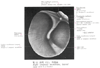

前ツチ骨ヒダ【ぜんつちこつひだ】 Fold extending from the base of the handle of malleus as far as the anterosuperior portion of the tympanic ring. It contains the anterior portion of the chorda tympani, the anterior process of malleus, and the anterior ligament of malleus.(ツチ骨柄の底部より鼓室輪の後ろ上部へいたるヒダ。鼓索神経の後部を含む。 (Feneis))